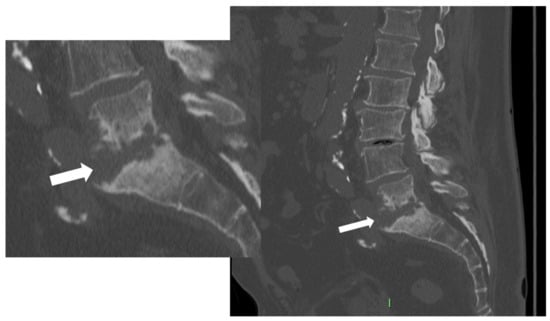

Figure 3. CT, sagittal reconstruction (magnification on the left), of a 77-year-old female with L5-S1 pyogenic spondylodiscitis characterized by thick endplates erosions (arrows).

As the infection progresses, CT may show soft tissue replacement of the bone. The involvement of the bone can result in erosive changes to the end plates (Figure 3).